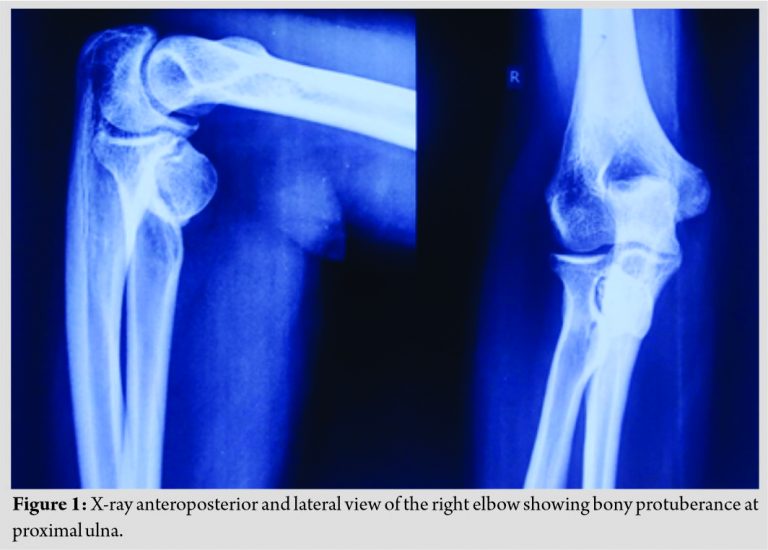

We present a case of a 35-year-old male who came to the orthopedics outdoor patient department with a complaint of swelling in the right elbow and restricted range of movement of elbow joint for 3 months. On local examination, a swelling was found, which was of 3 cm × 3 cm in size, hard, non-fluctuant, not mobile, was attached to the underlying bone, non-tender, with normal skin without any neurovascular deficit. A terminal restriction of the flexion of the right elbow joint was noticed, which was about 130 degrees and restricted pronation was found to be 65 degrees at proximal radio-ulnar joint while other movements were found to be normal. A provisional diagnosis was made based on clinical findings, radiographs, and a computed tomography (CT) scan. X-ray (anteroposterior and lateral view) (Fig. 1) of the right elbow showed a solitary external bony protuberance at proximal ulna around 5 mm distal to the coronoid process.